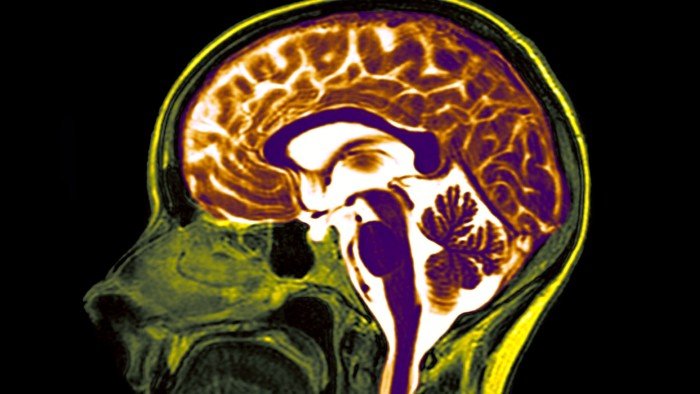

The arachnoid membrane takes its name from its spider weblike texture. It is one of three layers that protects the brain and spinal cord. Mine had been damaged at some point, creating a cyst that was filled with spinal fluid. It was putting immense pressure on my brainstem.

Arachnoid cysts are most often identified in children with developmental problems, and they are usually found at the front of the brain. It is rarer to discover one at the rear of the skull in a middle-aged man. No one could explain why I had the cyst. It may even have been there since birth. I visited two neurosurgeons after it was discovered in late 2022 and both recommended leaving it where it was as, at my age, the risks of operating in that region of the brain outweighed the benefits. But by February the following year a new scan showed that it had grown significantly.

I could see for myself from the MRI images delivered to an app on my phone that the white orb was now bigger than before, and it was muscling my brainstem off its centre. By then, I had started suffering vertigo-like symptoms and my balance was faltering. A friend I hadn’t seen for 20 years wondered whether I could hold my drink like I used to on seeing me stagger after only a couple of beers.